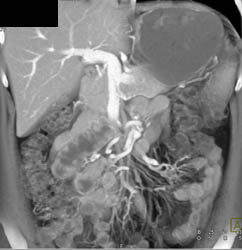

Portal Hypertension With Increased Flow Into Mesenteric Vessels